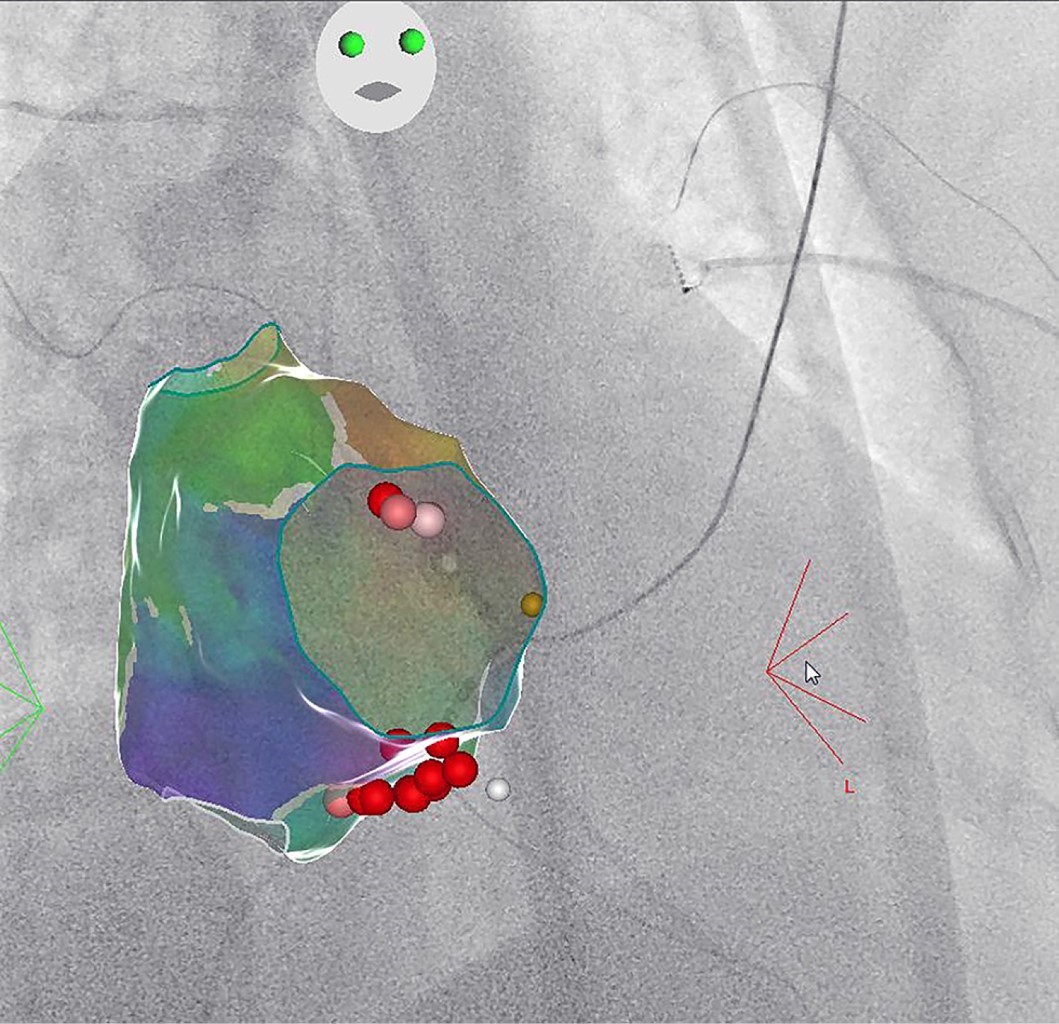

Reducción de la exposición a la radiación en un laboratorio de electrofisiología con el módulo CARTO-UNIVU™

La ablación por radiofrecuencia es una técnica eficaz y segura para el tratamiento de diferentes tipos de arritmias. La ablación por radiofrecuencia se realiza mediante fluoroscopia, una guía de navegación estándar, que está asociada con la exposición a la radiación y sus efectos nocivos bien reconocidos para los pacientes y para el personal de laboratorio. En la última década, los sistemas de mapeo electroanatómico han experimentado un fuerte desarrollo. A pesar de sus indiscutibles ventajas, no incluyen información obtenida por fluoroscopia en tiempo real. El módulo CARTO-UNIVU™ aborda esta importante limitación, ya que combina imágenes de fluoroscopia con el mapeo eletroanatómico tridimensional (3D) en una sola vista 3D, lo que permite una reducción pronunciada de la exposición a la radiación. Presentamos cuatro casos de nuestra primera experiencia en un solo centro con el nuevo módulo CARTO-UNIVU™.

Figura 4